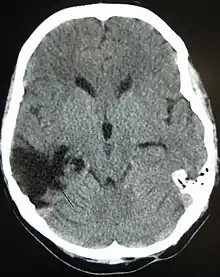

One type of focal injury, cerebral laceration, occurs when the tissue is cut or torn.[37] Such tearing is common in orbitofrontal cortex in particular, because of bony protrusions on the interior skull ridge above the eyes.[31] In a similar injury, cerebral contusion (bruising of brain tissue), blood is mixed among tissue.[23] In contrast, intracranial hemorrhage involves bleeding that is not mixed with tissue.[37]

Hematomas, also focal lesions, are collections of blood in or around the brain that can result from hemorrhage.[11] Intracerebral hemorrhage, with bleeding in the brain tissue itself, is an intra-axial lesion. Extra-axial lesions include epidural hematoma, subdural hematoma, subarachnoid hemorrhage, and intraventricular hemorrhage.[38] Epidural hematoma involves bleeding into the area between the skull and the dura mater, the outermost of the three membranes surrounding the brain.[11] In subdural hematoma, bleeding occurs between the dura and the arachnoid mater.[23] Subarachnoid hemorrhage involves bleeding into the space between the arachnoid membrane and the pia mater.[23] Intraventricular hemorrhage occurs when there is bleeding in the ventricles.[38]